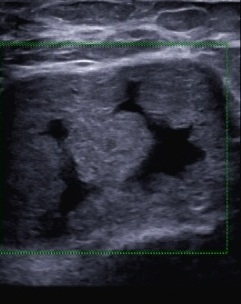

Etwa ein Jahr später wurde die Patientin wieder vorstellig. Sie hatte zwischenzeitlich eine Brustvergrößerung mit Eigenfett vornehmen lassen und bat um Kontrolle einer störenden Abflachung im unteren Bereich der rechten Brust (Abb. 3–5). Die sonografische Untersuchung war unauffällig, lediglich die normale Befundung nach derlei Eingriffen konnte dokumentiert werden (Abb. 6–8).